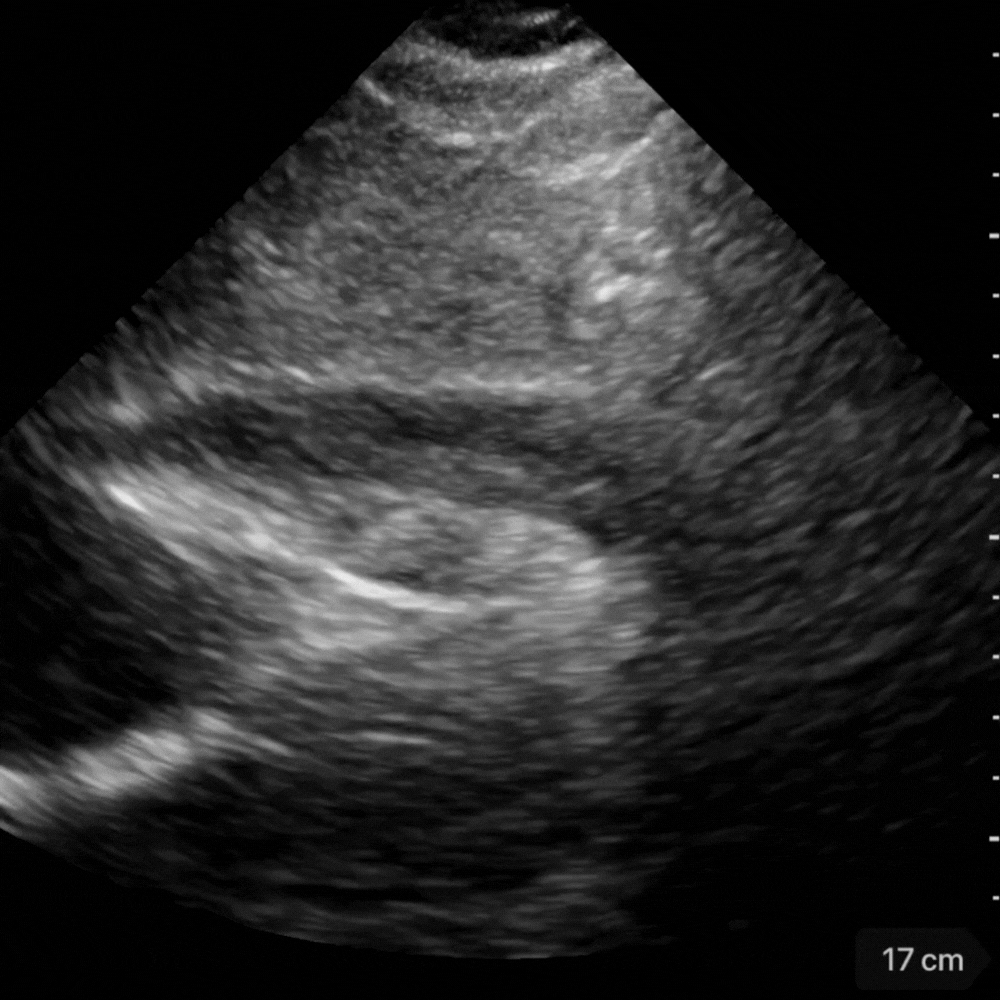

Vue sous-costale

Fenêtre prioritaire chez le patient instable ou en arrêt.

Le liquide apparaît comme une bande noire entourant le cœur, le plus souvent postérieure.

C’est ici que l’on détecte les premiers signes de collapsus du ventricule droit ou de l’oreillette droite.